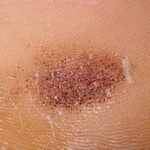

- Patients present with an irregular dark macule over the heel .

Examination reveals a blue-to-black macule or patch ranging in size from a few millimeters to several centimeters in diameter.

- On close inspection, multiple petechiae are centrally aggregated with a few scattered satellite macules.

- The dyschromia often is in a horizontal distribution; however, both circular and oval lesions may occur.